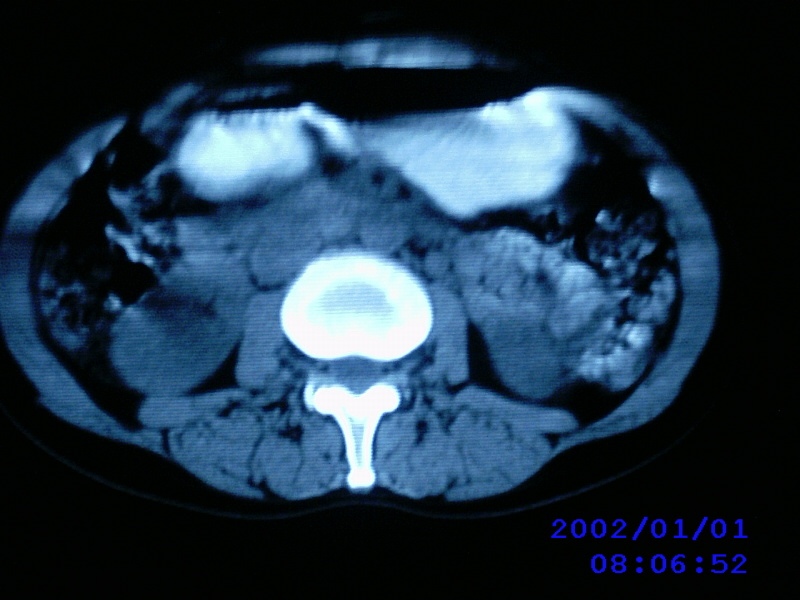

患者,女性,44岁,上腹部疼痛1个多月。b超提示胰头区域有低密度占位性病变。

考虑胰头癌伴肝门腹主动脉旁淋巴转移

老师病人没有黄疸,没有发烧,只是有点畏寒,中上腹部痛,b超提示胰腺没有问题,只是第二肝门近胰头部见一大小约3.7cmx2.5cm椭圆形低回声,形态欠规则,边界可见.

考虑胰头癌并肝门区及腹膜后淋巴结转移。

考虑胰头癌并肝门区及腹膜后淋巴结转移。还是要增强。

考虑胰头癌并胰头周围及腹膜后淋巴结转移。

胰头区域囊肿?胰腺囊腺瘤?建议增强扫描。

考虑胰头癌并淋巴结转移可能性大,造影剂可否考虑减低一下浓度,从而减少伪影